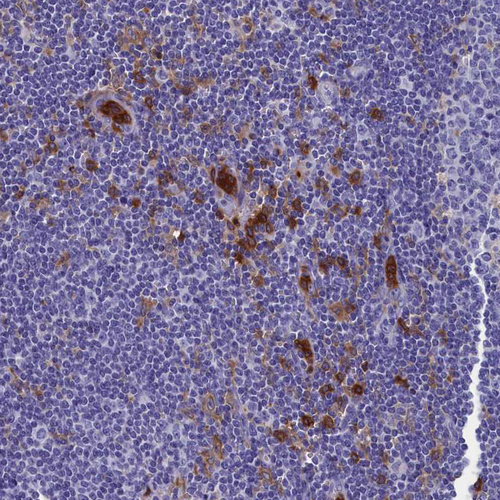

Immunohistochemistry analysis in human bone marrow and skeletal muscle tissues using HPA041899 antibody. Corresponding TYROBP RNA-seq data are presented for the same tissues.